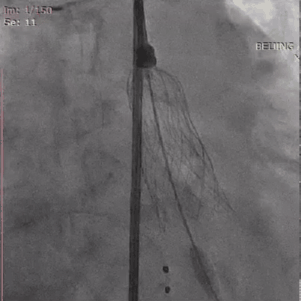

从三叶瓣重度钙化到二叶瓣畸形的根部解剖,从单纯主动脉瓣反流到入路极端迂曲挑战的案例。TaurusOne凭借其优异的柔顺性,支撑力强及内外层双侧裙边的特点,都能从容应对复杂的临床患者解剖结构。从患者的临床选择到术后的长久获益,从手术入路的种类到术中操作的注意事项,从围术期卒中的循证医学到术后的抗凝抗栓用药规范,在线专家共同交流彼此中心的围术期TAVR经验和分享现阶段经导管主动脉瓣置换的诊疗策略。针对当前TAVR领域多个热点学术问题进行了热烈的讨论,现场可谓精彩纷呈、高潮迭起。专家们纷纷借此契机相互交流探讨,分享各自的单中心经验,力求进一步提升TAVR手术的安全性和有效性,为主动脉瓣相关疾病的患者带来长远综合获益。